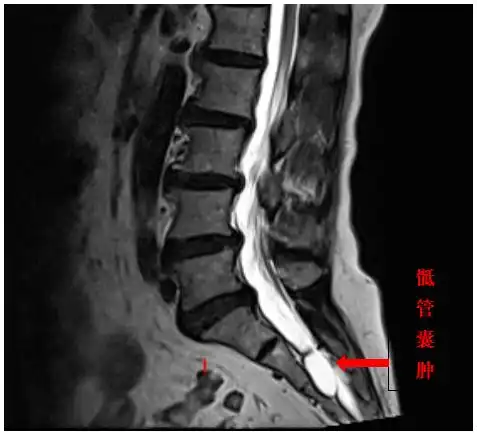

进行性后背部疼痛骶尾椎脊索瘤

骶尾部肿瘤及肿瘤样病变影像诊断

骶尾椎病变的诊断思路

骶尾部脊索瘤如何进行影像诊断?一篇搞定!

骶尾部肿瘤